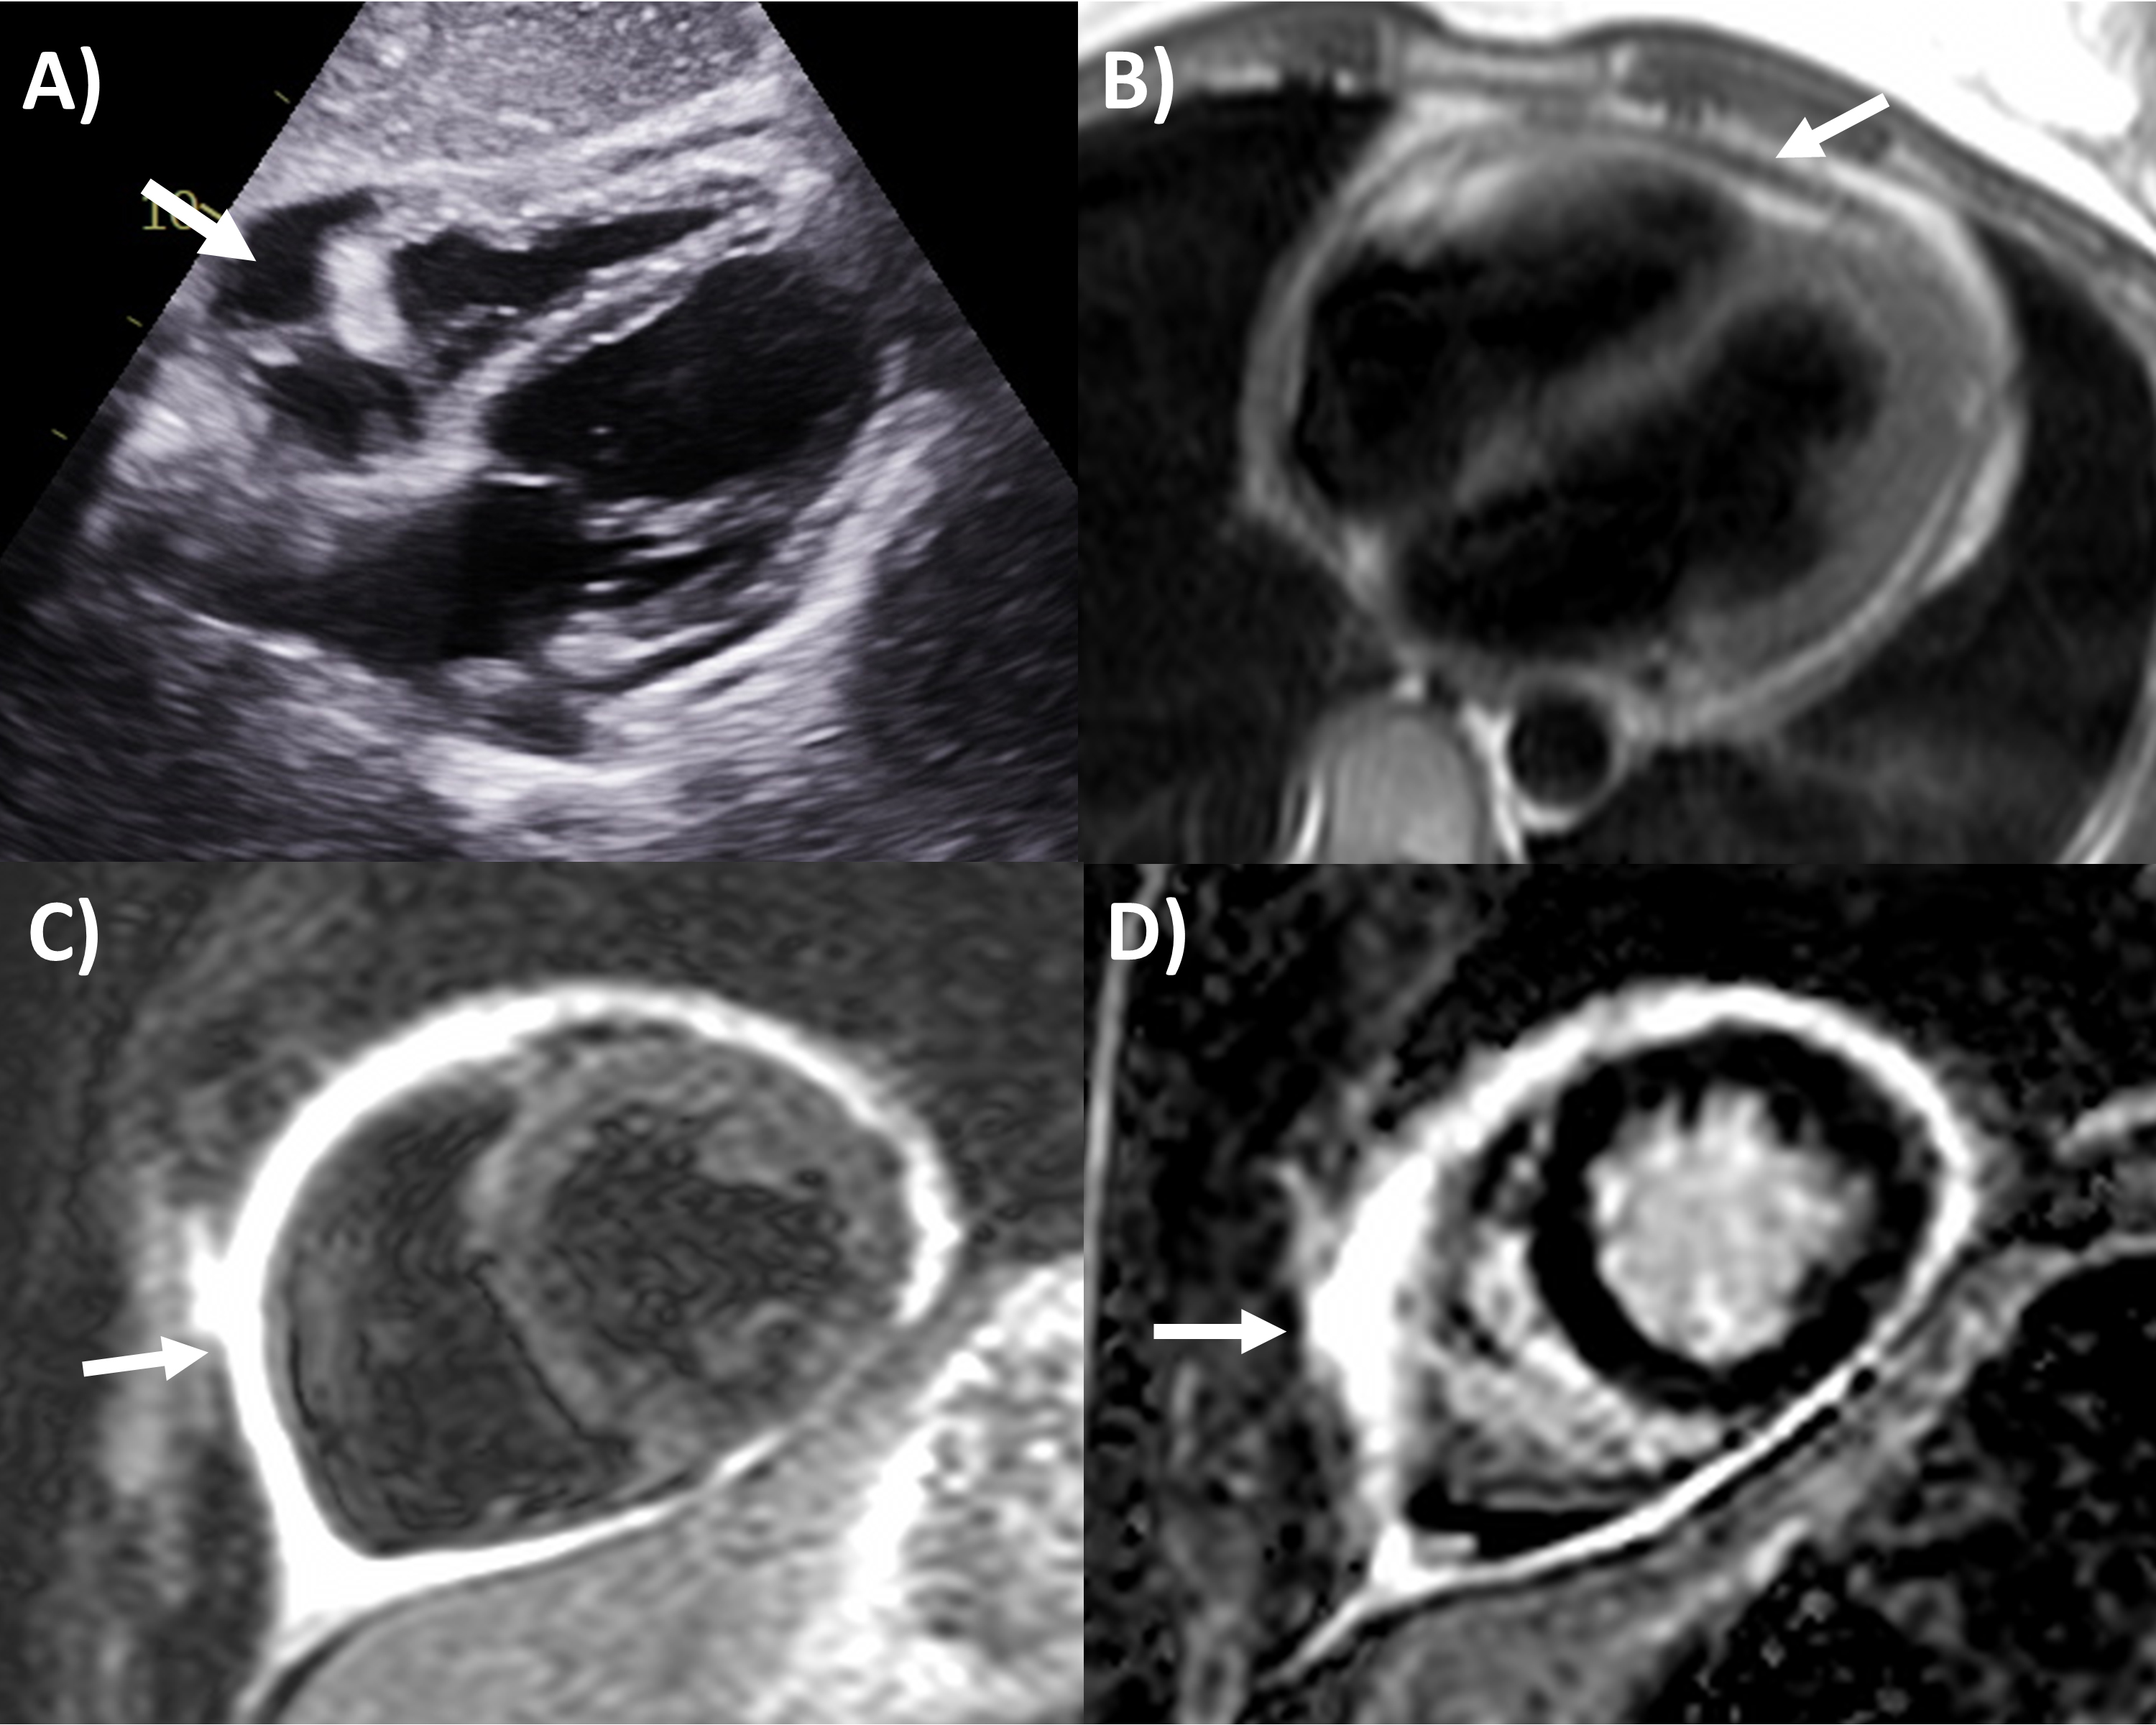

Although echocardiography can identify the presence of pericardial masses, the information it provides can be limited in terms of tissue characterization as well as the extent and spread of the mass. However, some typical tumor features are as follows: haemangioma are usually hyperechoic with septae; lymphangiomas appear heterogenous and hypoechoic with septae, lipomas are usually circumscribed and echogenic; teratomas are usually heterogeneous with both cystic and calcific echogenic areas; lymphoma are usually hypoechoic with effusion; while mesothelioma is usually associated with pericardial thickening and effusion [31, 56]. For pericardial cysts, a hypoechoic space next to the heart chamber border most commonly the right atrium is seen on echocardiography, with lack of blood flow within demonstrated by Doppler or intravenous contrast [31, 57]. Pericardial cyst and diverticula differ where the former has a constant size with altering shape while the other changes in both size and shape with body posture and breathing. Echocardiography may provide guidance in aspiration and drainage of pericardial cysts as well [58].

CT has greater ability for tissue characterization than echocardiography, and is able to assess the extent, local or distant spread of masses, lymph node involvement and many pericardial tumors have associated effusions that are hemorrhagic or exudative [31]. Hemangiomas appear heterogenous with contrast enhancement; lymphangiomas are heterogenous with low attenuation and septae; lipoma have low fat-level attenuation that is circumscribed, and sometimes can surround coronary arteries; teratomas usually have contain areas of calcification and fat; lymphoma are hypoattenuating with contrast enhancement; fibromas are homogeneous with no or minimal enhancement given lack of vascularity; sarcomas are broad-based masses which invade adjacent structures; and mesothelioma is seen as diffuse irregular pericardial thickening with effusion [31, 56]. Pericardial cysts are seen as a well-circumscribed homogeneous mass with thin wall on CT, with fluid density, unaffected by intravenous contrast (Fig. 4) [59, 60].

Fig. 4.Multi-modality imaging tissue characterization of pericardial cyst (arrows in all panels) adjacent to the right atrium. (A) Computed tomography axial slice, cyst was 10 Hounsfield units. (B) Magnetic resonance imaging (MRI) steady-state free precession bright blood sequence axial slice, cyst has increased signal. (C) MRI T2-short tau inversion recovery sequence, cyst has high signal. (D) MRI late gadolinium enhancement sequence axial slice, cyst has low signal.

MRI’s main advantage amongst imaging modalities is its ability in tissue characterization, and this is no different when applied to pericardial masses. Depending on tumor extension, the pericardium or myocardium may show thickening, or pericardial effusions, the latter often exudative or hemorrhagic with high signal intensity on T1-weighted sequences [31]. On T1-weighted, T2-weighted and gadolinium enhanced sequences, many tumors have low, high and high signal intensities [14, 31, 61, 62, 63]. Hemangiomas generally appear heterogeneous on all sequences, while lipomas have high signal intensity on all sequences, however its signal can be uniquely suppressed on fat-saturation pulse sequences. Fibroma have low vascularity and therefore have low signal intensity on T2-weighted sequence and none to minimal enhancement on gadolinium enhanced sequences. Mesotheliomas appear homogeneous on T1-weighted but have heterogenenous elevated signal on T2-weighte and gadolinium enhanced sequences. Of note, some studies have suggested heterogenous gadolinium uptake to indicate areas of increased lesion nodularity, growth and/or necrosis [64]. Pericardial cysts also appear as a well-circumscribed homogeneous mass with thin wall on MRI, displaying hypointense signal on T1-weighted sequence unless there is an exudative or hemorrhagic component, with hyperintense signal on T2-weighted sequence and no signal on LGE sequence (Fig. 4) [31, 65]. Lastly, pericardial hematomas show hyperintense, heterogeneous and hypointense signal on T1 and T2 weighted sequences in the acute, subacute and chronic stages, and no signal on LGE sequences regardless of timeframe [31].